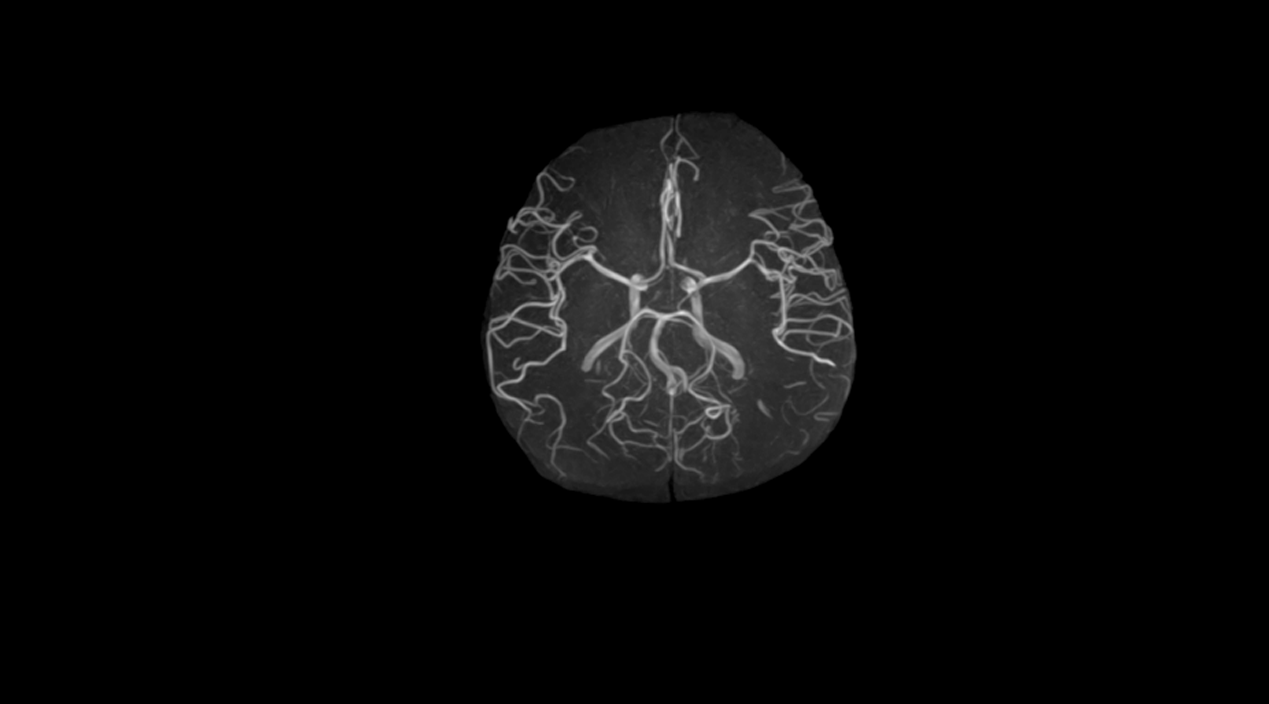

1.5T MRI

Kangda Colorful Model: Farol 1.5T

Product Introduction

Product highlights

1.5T superconducting magnet technology: using "Zero Boil-off " superconducting magnet technology;

Fine shimming system: Adopting a fine shimming system to maximize theeffectiveness of the magnet;

16 channel fiber optic RF signal digital transmission technology: Advancedfiber optic RF signal digital transmission technology is sampled to eliminatesignal loss and distortion caused by MR signals during transmission;

CS compression perception acceleration function: greatly improvesscanning speed while ensuring image quality;

High performance gradient system: Adopting a high-performance gradient system with a maximum intensity of 35mT/m, extremely low vortex flow ensures image clarity;

Artificial Intelligence Scanning Assisted Diagnosis Technology;